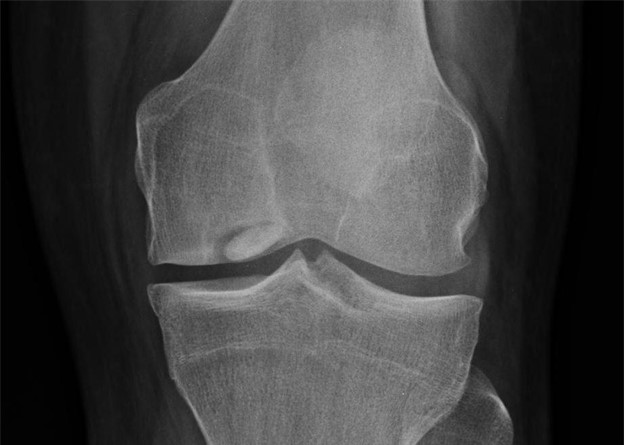

Bipartite or Multipartite Patella

The patella typically arises from a single center of ossification. In some cases, it arises from two or more centers with connection of these segments by fibrous segment of tissue. Incidence is 90% male, and it is typically unilateral.9 Presentation is typically characterized by localized pain and swelling. X-ray is diagnostic, showing incomplete ossification. Most cases of bi- or multipartite patella are found incidentally.19 Rest of activity for a prolonged period and use of NSAIDS is indicated to manage conservative, and many patients have relief in three-four weeks. If necessary, orthopedic surgery may be necessary in some patients, but evidence on the optimal approach is lacking, and there are at least seven approaches found in the literature.

This is a subtle bipartite patella with lateral abnormality

Case courtesy of Dr. Sumit Verma, Radiopaedia.org. From the case rID: 74103

Case courtesy of Dr. Aditya Shetty, Radiopaedia.org. From the case rID: 27156